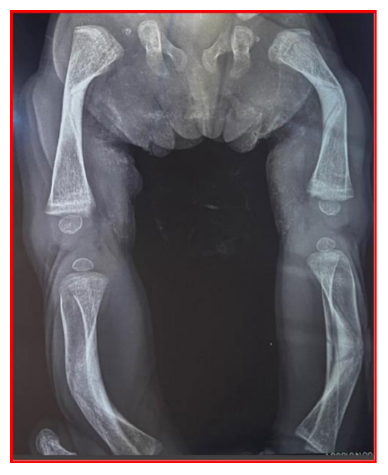

In the reported case, the infant presented with prenatal and postnatal findings suggestive of Stuve-Wiedemann syndrome, including intrauterine growth restriction, bowed long bones, feeding difficulties, recurrent respiratory distress, and episodic hyperthermia. Physical examination revealed dysmorphic features, hypotonia, fixed flexion deformities of the fingers, and shortened, bowed extremities, with growth parameters below the third percentile for age.

The authors note that molecular confirmation can help distinguish Stüve-Wiedemann syndrome from other skeletal dysplasias with overlapping features (e.g., campomelic dysplasia) and clarify its relationship to Schwartz-Jampel syndrome type 2, which is now considered part of the same clinical entity.